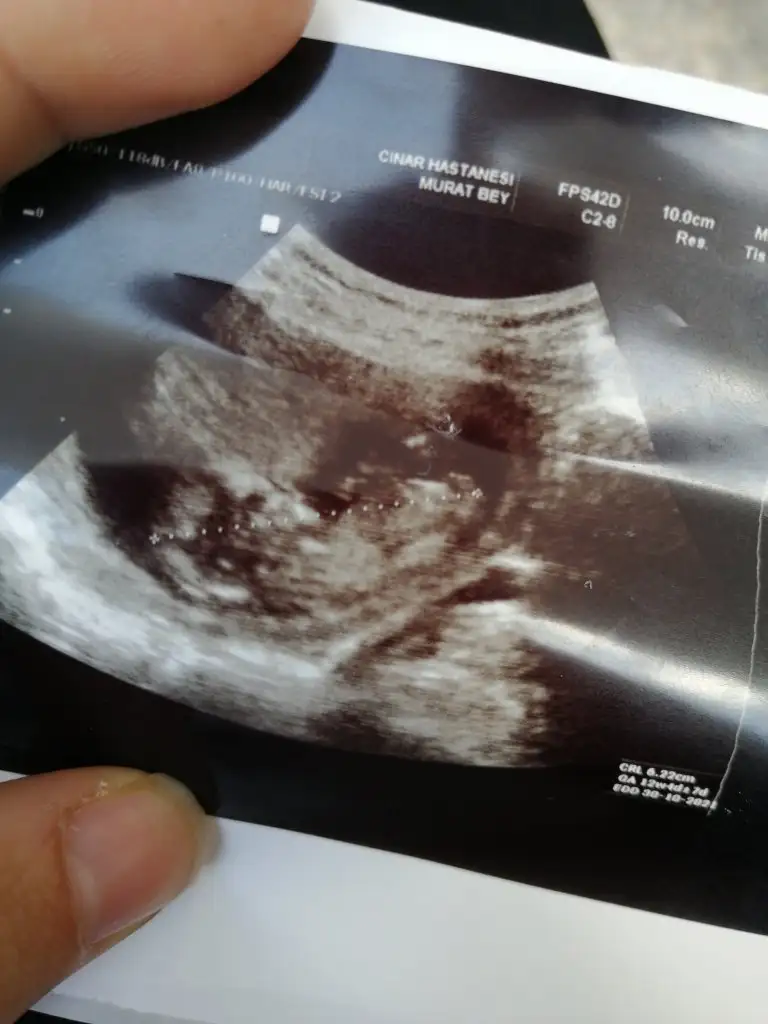

dr soylemeden siz gorun genital nub teorisi ( bebegin cinsiyeti)

12+3 bankada tahmin de bulunurmusunuz